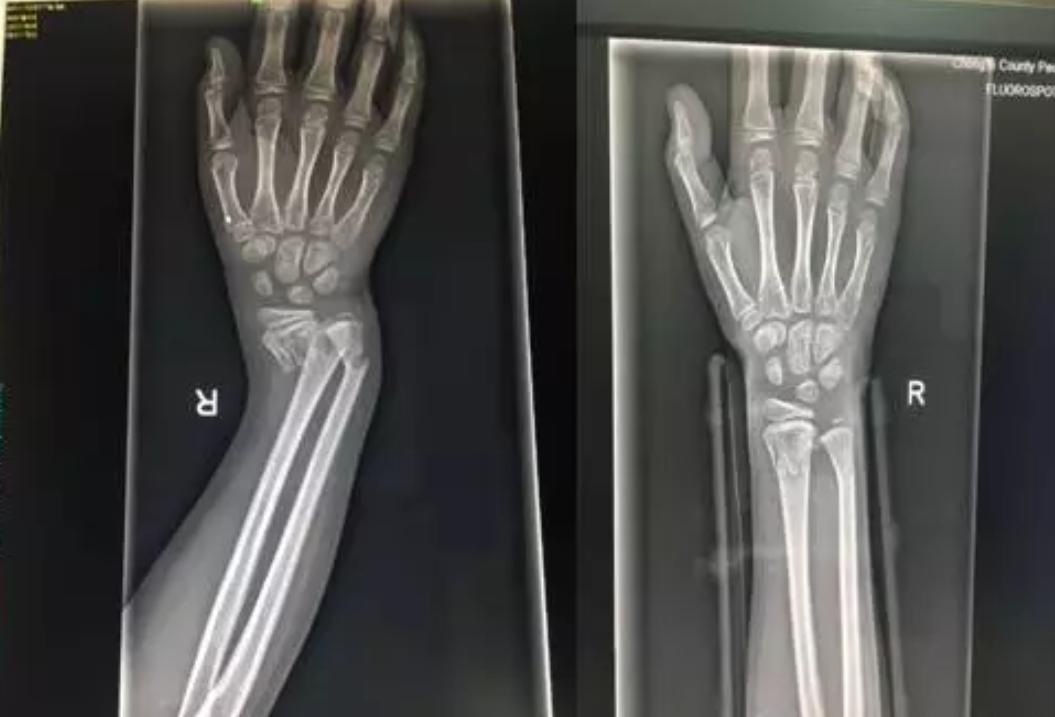

由上图可以看出孩子的右手段明显的畸形

DR片提示右桡尺骨远端骨折。因为骨折严重错位,孩子疼痛的已经脸色惨白,我们将治疗方式提供给患儿家属,征得同意后实施正骨手法复位。准备好一切所需要的物品,如绷带、夹板、扎带、棉垫、压垫。孩子很坚强,积极配合,吴医生与朱医生默契配合,在场的人都屏住呼吸,希望医生可以一次复位成功,避免孩子再承受更多的痛苦。牵引、复位一气呵成。

在场的人都松了一口气,固定夹板,交待注意事项,复查。让我们看看复查前、后的DR片吧!